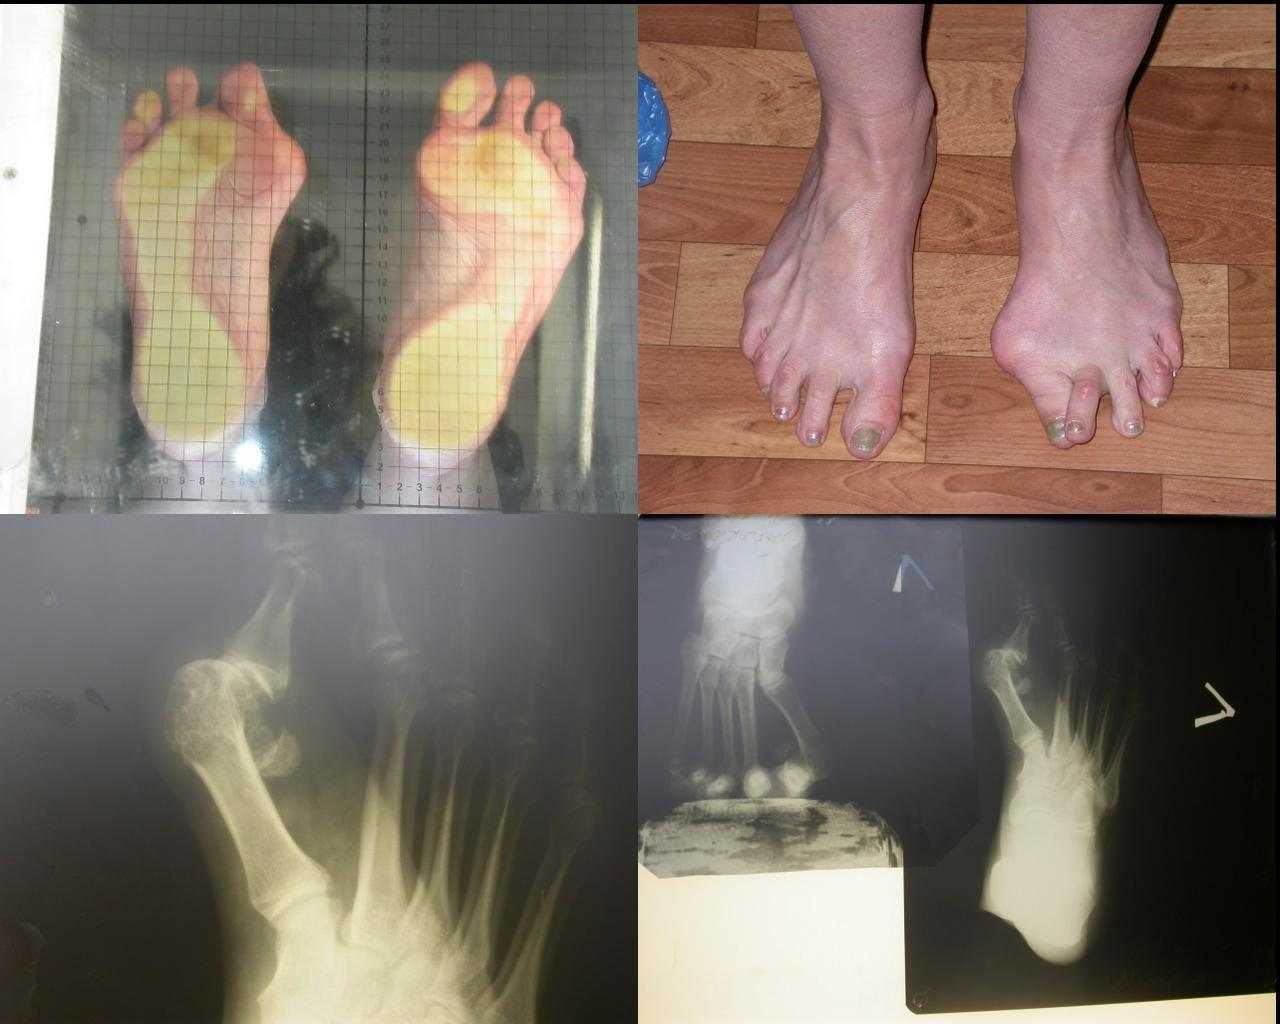

[Ortho] СИНДРОМ ЭЛЛОРСА-ДАНЛО

посылаю коллаж